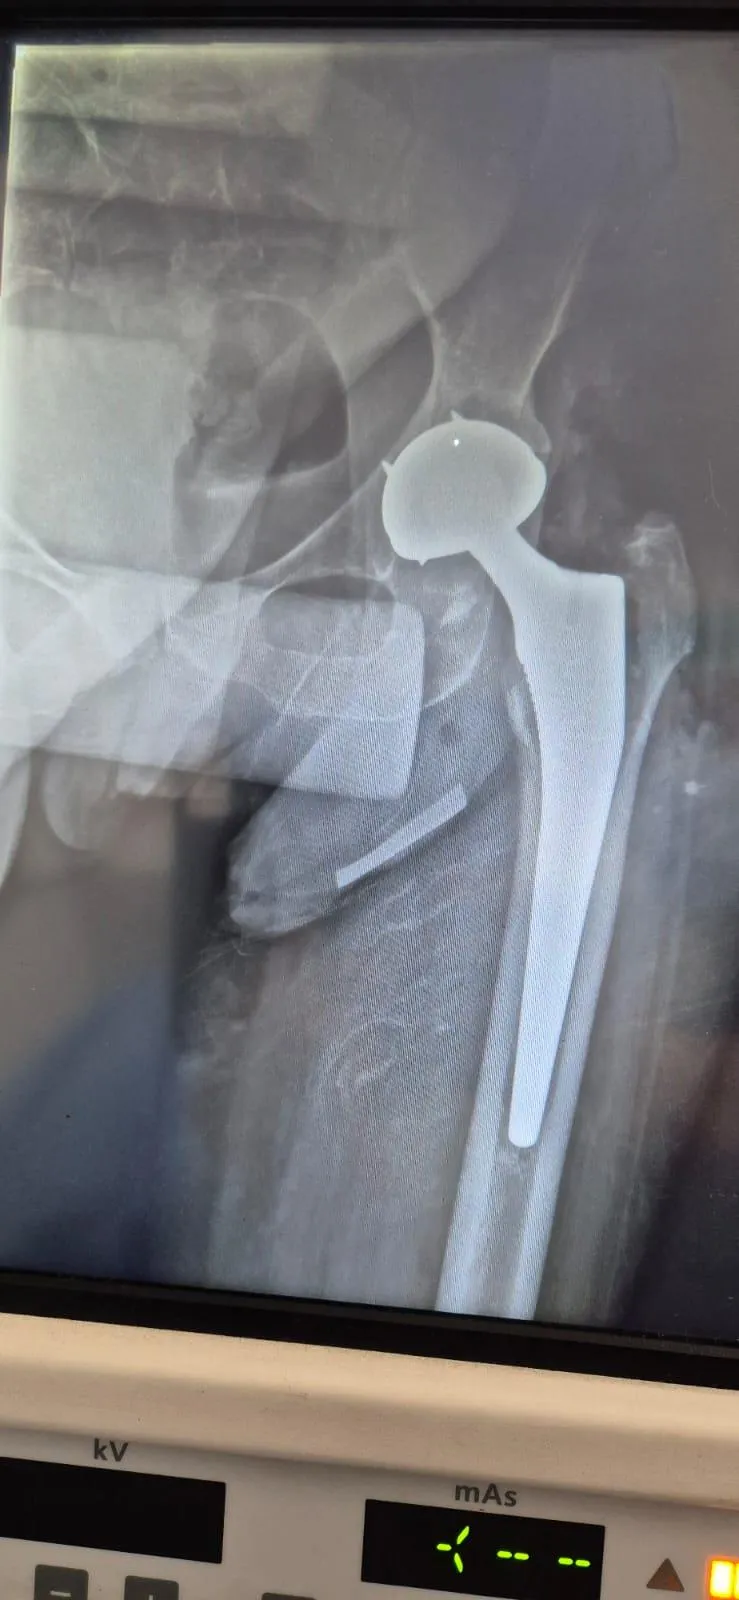

Prótesis de Cadera

Complicación manejada con prótesis de doble movilidad

Paciente al segundo día postoperatorio. Complicación abordada mediante colocación de prótesis de doble movilidad.